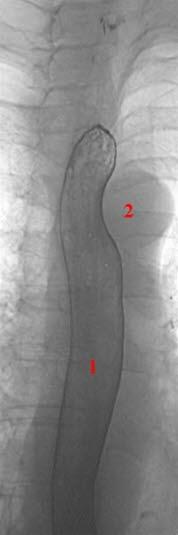

Røntgenbilde av normal tarmMesenteriell iskemi eller tarmiskemi betyr nedsatt blodforsyning (iskemi) til tarmen (mesenteriet). Det skyldes som regel at en blodpropp tetter til en blodåre som forsyner deler av tarmen med blod. Alle kroppens vev er avhengig av konstant tilførsel av blod, og områder som mister sin blodforsyning, vil dø.